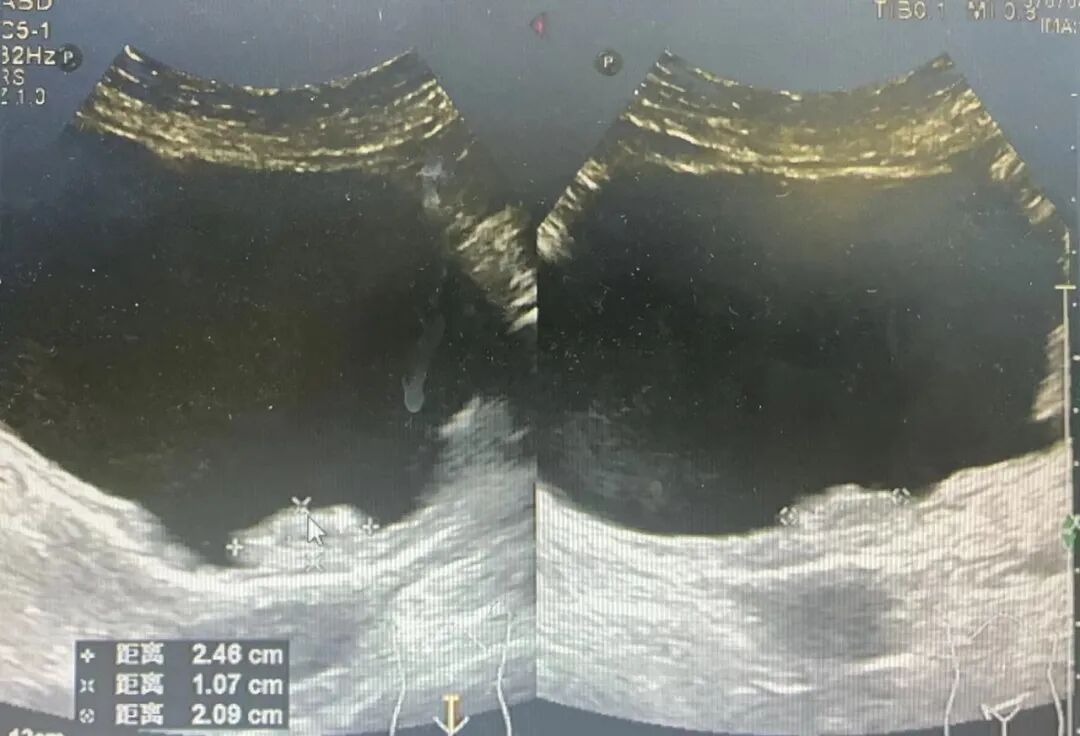

患者为60岁女性病人,因反复尿频、尿急、尿痛5月余入院治疗。经检查,患者膀胱后壁“蕈伞样”隆起,膀胱镜活检后,诊断为膀胱癌。

图片